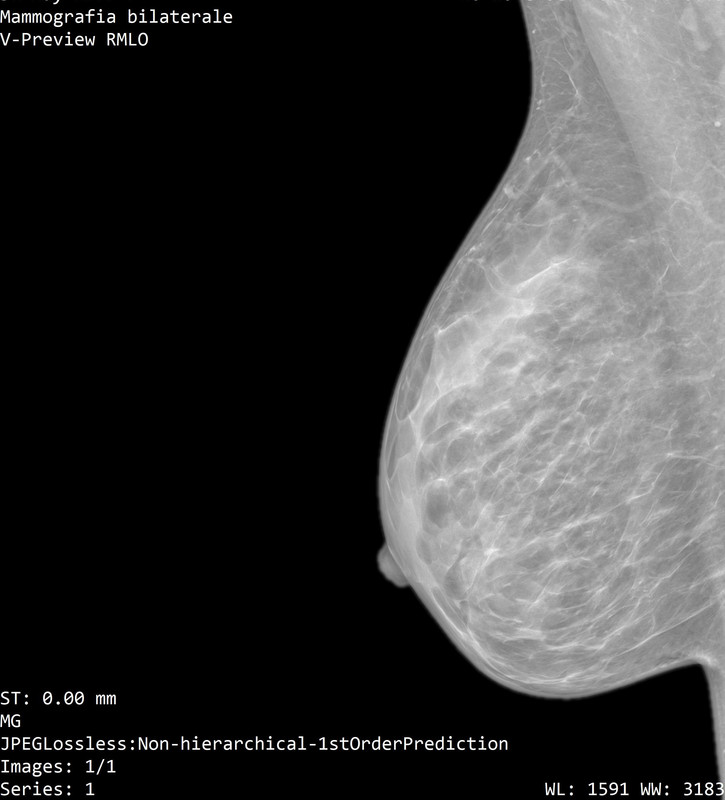

Onestamente non capisco neppure quale sia la mammella destra dalla sinistra...

Il referto dice:

"a dx al passaggio tra i quadranti inferiori e' meglio visibile un focolaio di microcalcificazioni, non riconoscibile con certezza all'ecografia mirata, meritevole di caratterizzazione mediante agobiopsia con sistema VAB sotto guida mammografica